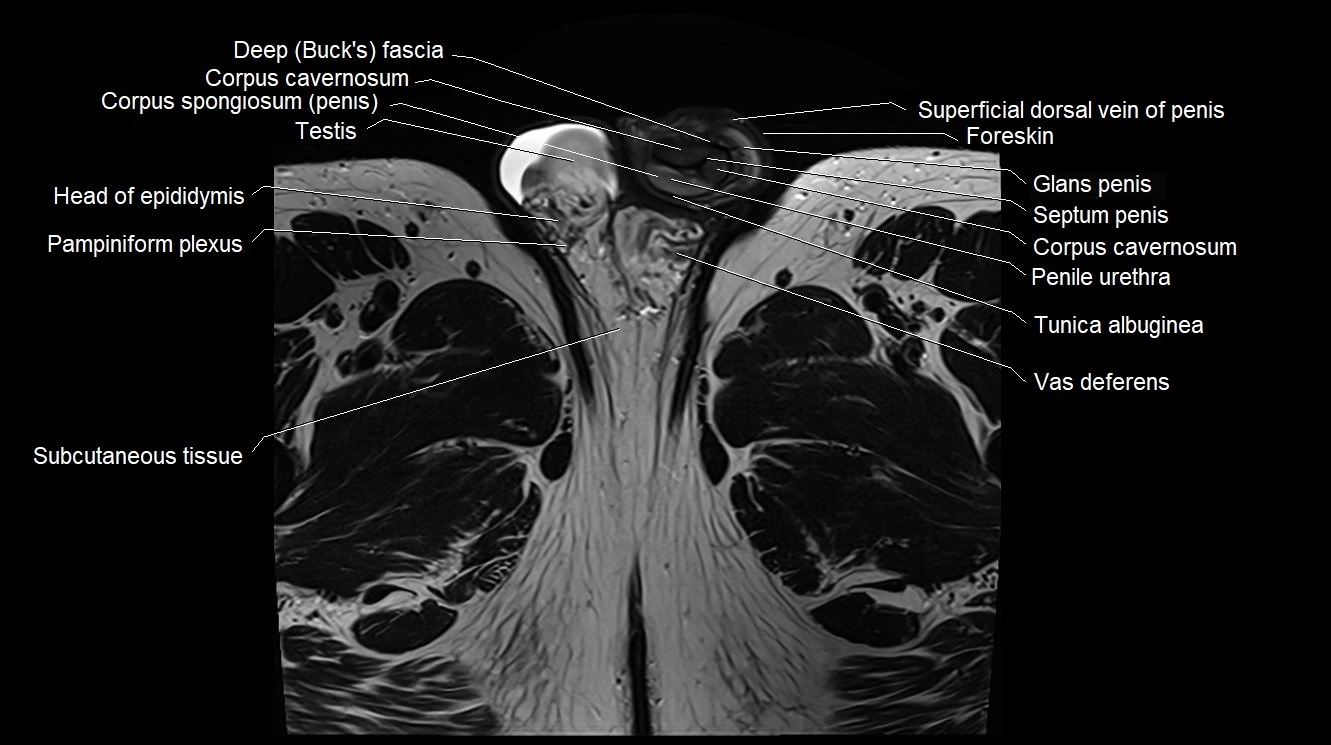

- Buck's fascia (Deep fascia of penis)

- Corpus cavernosum

- Corpus spongiosum

- Foreskin

- Glans penis

- Head of epididymis

- Pampiniform plexus

- Penile urethra

- Septum of the penis (Penile septum)

- Superficial dorsal vein of penis

- Testis

- Tunica albuginea (penis)

- Vas deferens